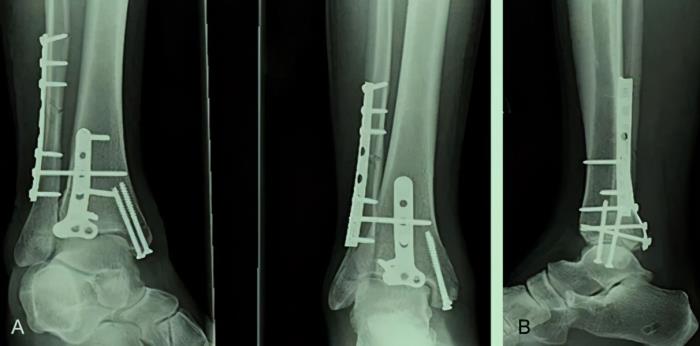

无论是谁,除去身体中的加固物体,比如骨折后加强用的钢钉与钛合金等,真正的骨灰不会超过1.5~2.5千克,这些骨灰,就很多朋友而言,仍然会埋入公墓,以供亲人吊唁纪念。